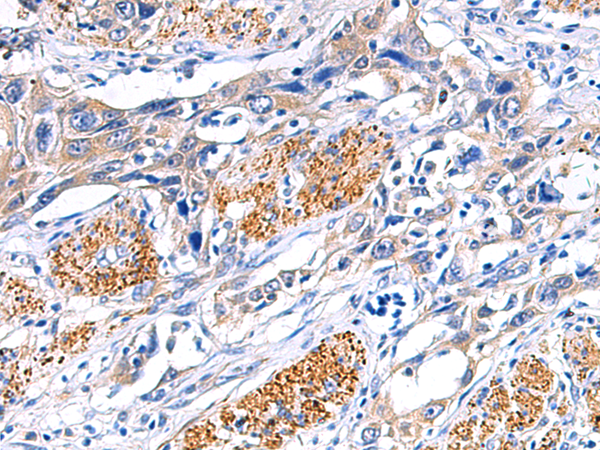

分类: 科研抗体货号: P06470别名: EVI1; MDS1; KMT8E; PRDM3; RUSAT2; MDS1-EVI1; AML1-EVI-1应用: WB,IHC反应种属: Human, Mouse